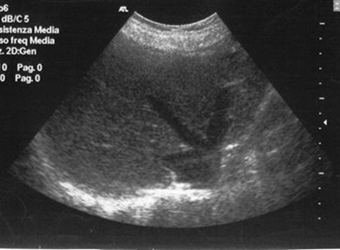

随着孕周增加,准妈妈的B超单上会出现越来越多新鲜的名词,这对于第一次怀孕的准妈妈来说,显然是一脸茫然,不知道每个词代表什么。今天我们来讲讲一侧股骨长…